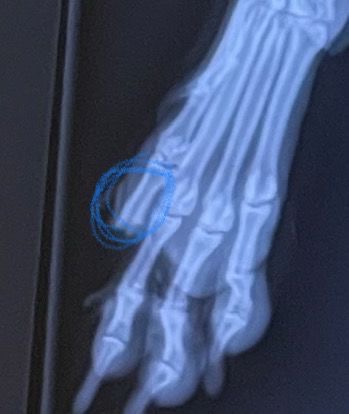

My human rushed me to the emergency vet. I had surgery the next day, and part of my bone was removed. I’ll never have my full paw again. Now, my human is left with a $5,000 vet bill.